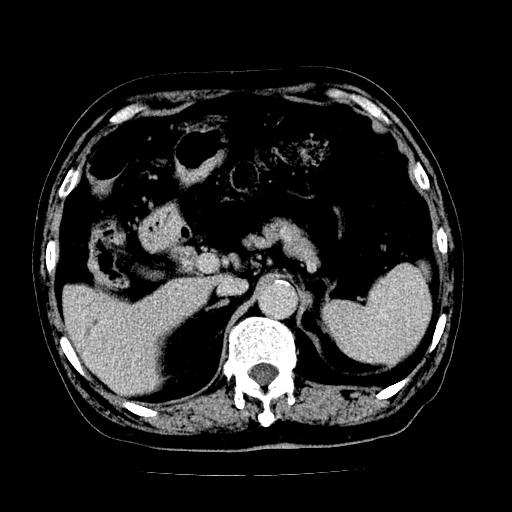

男,71岁,皮肤黄染四天。

肝内外胆管及胆总管上段扩张,考虑为梗阻所致,建议mrcp检查。

考虑胆总管癌并肝内外胆管扩张。

支持考虑胆总管癌并肝内外胆管扩张。 局部应薄扫。心包钙化。

胰腺上端胆总管内见软组织影,强化不明显,结合临床,还是考虑低位梗阻性黄疸,胆总管癌可能性大